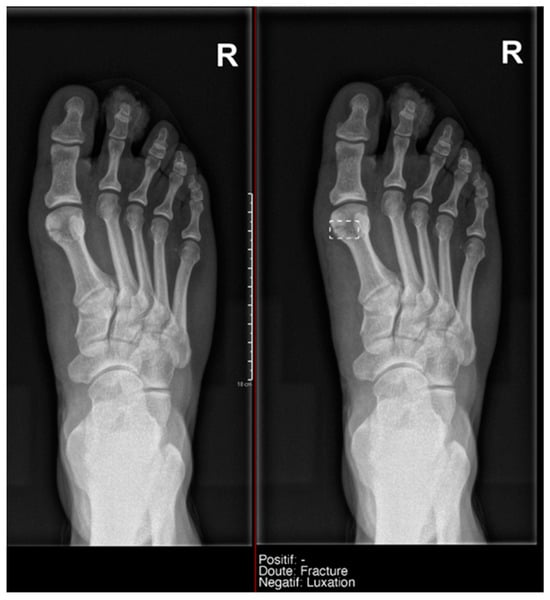

- Ankle and foot: On six occasions, Milvue marked the fracture variable as doubtful in cases with a bipartite medial sesamoid (two patients), an accessory sesamoid at the base of the 5th metatarsal, synphalangism, os peroneum, and os naviculare. (Figure 8).

- Hand: Milvue marked the fracture variable as doubtful in the case of multiple accessory ossicles.

- Wrist: On four occasions, Milvue marked the fracture variable as doubtful in cases of os paranaviculare, os trapezium secundarium, os ulnar styloid, and os paratrapezium. However, Milvue did not detect fractures in three cases of os ulnar styloid, two cases of accessory ulnar styloid, nor in cases of os hypolunatum and os epilunatum.